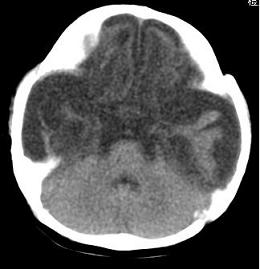

男,4个月大,2个月前无诱因下四肢抽搐、伴呕吐,近2天来抽搐频发,伴发热。查体:双眼疑视,神萎、纳差;颈抵抗,四肢张力高。

病史太长了,原因不好定,不过如果2个月前小儿正常的话可考虑积水型无脑畸形,积水型无脑畸形小儿刚生下来表现可正常,存活一两个月后出现症状.

另不除外缺血缺氧性脑病,感染等改变

2个月前缺血缺氧性脑病留下的后遗症。

脑出血后,软化灶形成了。脑发育不良

支持缺血缺氧性脑病留下的后遗改变(脑软化灶+脑发育不全+双侧慢性硬膜下积液+小头畸形)。

支持考虑缺血缺氧性脑病留下的后遗改变。

要注意化脓性脑膜、脑炎,硬膜下积脓,脑积水的可能,建议腰穿助诊。